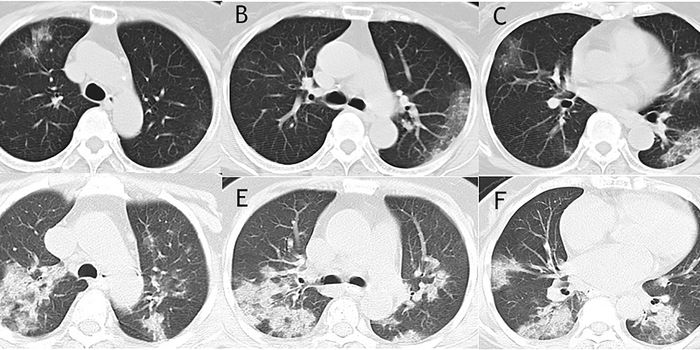

MAR 25, 2020Health & MedicineCT scans from 27 patients that first contracted Cornonavirus in Wuhan, China reveal signatures in the lungs that could h ...